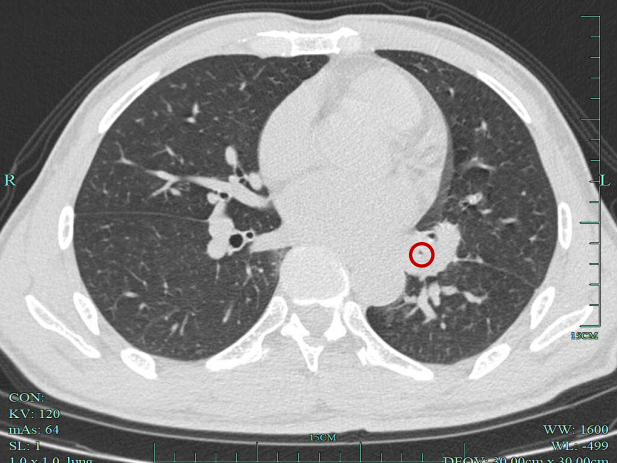

接诊的汝触会主任仔细问诊及查体后,发现张师傅年轻时有过肺结核感染史。结合这一重要信息,汝医生为其安排了胸部CT检查。很快,胸部CT影像提示多发囊状支气管扩张,更糟糕的是,这些扩张的支气管里已经被痰栓堵得严严实实。

患者胸部CT可见支气管内痰液堵塞,多发囊状支气管扩张